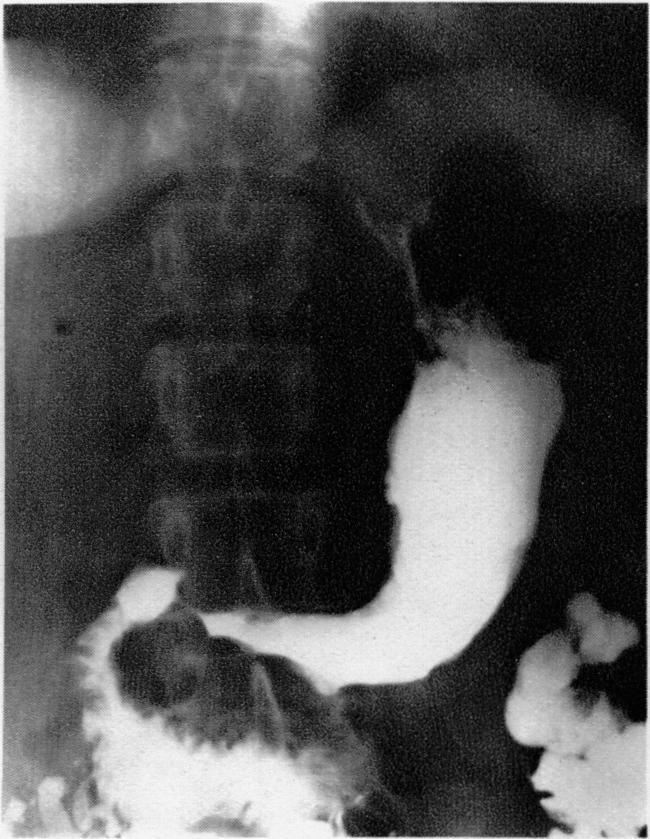

Carcinoma of the Stomach.

Br Med J. 1937 Nov 13;2(4010):949-978.1. doi: 10.1136/bmj.2.4010.949.